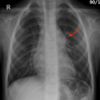

TEP

88

¿Qué es el signo de la joroba de Hampton?

Opacificación pleural en "domo" Secundario a infarto y hemorragia

89

Joroba de Hampton = TEP